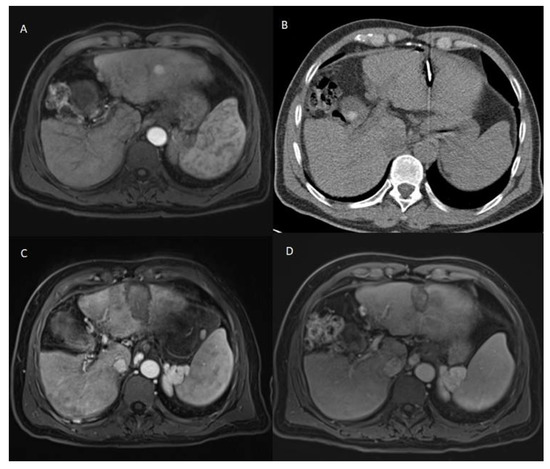

The patients who developed LTP or IDR were treated by MWA, LITT, or TACE, depending on the number, size, and location of the new HCC lesions. The decision was taken by the multidisciplinary tumor board. Examples of Patients’ cases are shown in Figure 1 and Figure 2.

Figure 2. 69 years old male patient with chronic hepatitis C virus, liver cirrhosis, and HCC lesion in the right liver lobe, who was treated with LITT. (A) Pre-treatment CEMRI showed an arterial hyperenhancement of the lesion. (B) 24 h post-ablation CEMRI showed a large post-ablation zone, and the lesion was fully ablated. (C,D) At the 3-months post-ablation CEMRI, the size of the ablation zone was getting decreased without LTP, but there was a hyperenhancement in untreated liver segment (white arrows), which was correlated with IDR. TACE was performed to treat the recurrent HCC and the patient lived for 33 months after LITT until death.